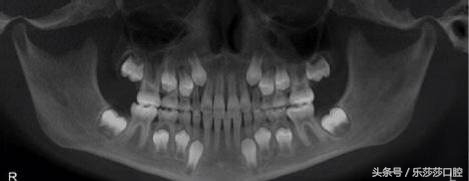

一、儿童换牙时期的头骨:这个阶段「恒牙」未萌出,和「乳牙」同时存在。所以剥离「骨壁」以后可以同时看见乳牙和隐藏在乳牙之下等待萌出的恒牙。

小时候你看见自然脱落的乳牙没有「牙根」,其实是因为乳牙在脱落前「牙根」被吸收,为恒牙的萌出腾出骨内空间。